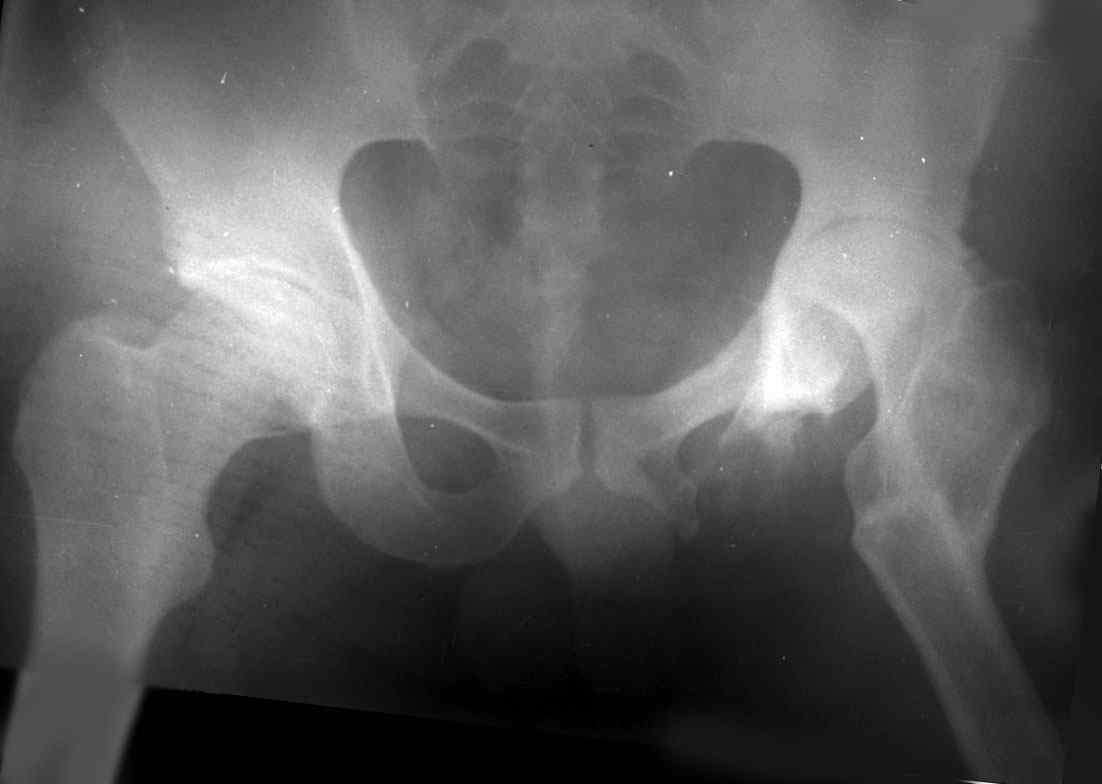

.........наверное не повезло. Но иногда это выход и очень хороший. М., 21 года спрыгнул в Армии с машины с исходом в гнойный коксит, свищевой формой в течении 1,5 лет. Операция проведена в 1988 году. результат хороший и сейчас и мы с пациентом хорошие приятели (Рентг-гр и фото прилагаю).